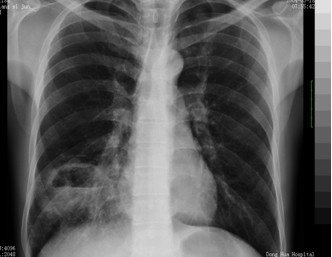

(2)肺结核:结核中毒症,状病程长,痰结核菌可(+)

http://webres.medlive.cn/upload/000/062/243